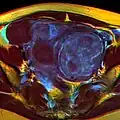

Diagnosis

Physical examination and ultrasound are sufficient for diagnosing uterine fibroids in the majority of people. When ultrasound findings are inconclusive, magnetic resonance imaging (MRI) may be able to confirm the diagnosis of uterine fibroids in most cases. In addition, MRI can identify benign uterine fibroids with atypical imaging features and fibroids with variant growth patterns. MRI can also identify other uterine (e.g. adenomyosis, endometrial polyps, endometrial cancer) and extrauterine (e.g. benign and malignant ovarian tumors, endometriosis) disorders that may mimic the appearance of uterine fibroids and/or contribute to the patient's symptoms.[38] However, a small proportion of uterine fibroids can mimic other malignant uterine tumors (e.g. leiomyosarcoma) on all available imaging modalities (e.g. ultrasound, CT, MRI and PET-CT).[38]

Malignant tumors of the uterine wall (e.g. leiomyosarcoma) are very rare. Findings suggestive of a malignant uterine tumor rather than a benign fibroid include, fast or unexpected growth (particularly after menopause), interruption/effacement of the endometrial stripe, lymph node enlargement, invasion of adjacent organs and metastases to distant organs (e.g. lung). MRI findings suggestive of a malignancy include nodular/ill-circumscribed tumor margins, intermediate/high T2-weighted signal intensity of the solid tumor components, regions with high signal T1-weighted sequences in keeping with subacute hemorrhage, fine/wispy enhancement of the solid parts of the tumor, and restricted diffusion on diffusion-weighted imaging (DWI).[38] A biopsy is rarely performed and if performed, is rarely diagnostic. Should there be an uncertain diagnosis after ultrasounds and MRI imaging, surgery is generally indicated.[39]